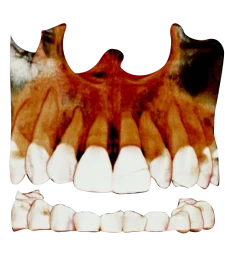

FOV 18×16 см, 300 μm

FOV 10×10 см, 160 μm

.

FOV 4×5 см, 70 μm

Технология AMF (Адаптивный движущийся фокус) выбирает оптимальный слой изображения для получения чётких панорамных изображений, что позволяет легко определить состояние пародонта пациента и локализацию поражения.